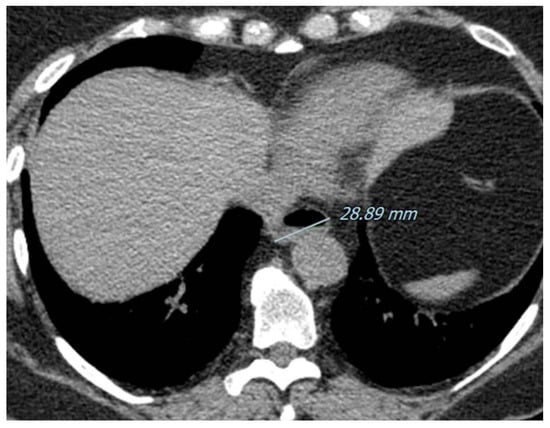

- Chaisson, N.F.; Hassoun, P.M. Systemic Sclerosis-Associated Pulmonary Arterial Hypertension. Chest 2013, 144, 1346–1356. [Google Scholar] [CrossRef] [PubMed] [Green Version]

- Strollo, D.; Goldin, J. Imaging Lung Disease in Systemic Sclerosis. Curr. Rheumatol. Rep. 2010, 12, 156–161. [Google Scholar] [CrossRef] [Green Version]